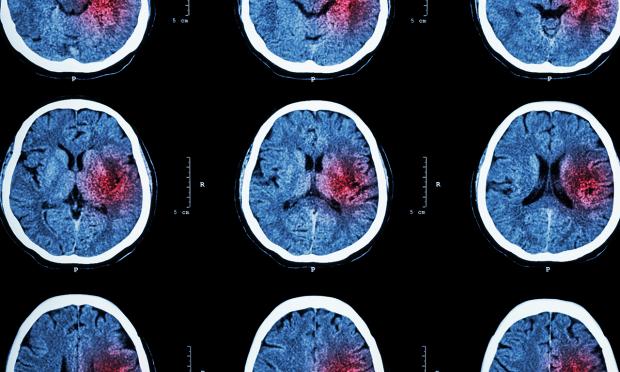

Vol 212, Issue 8: 4 May, 2020. Professor Richard Lindley is Medical co-Chair of the NSW Stroke Network. He talks about the Victorian Stroke Telemedicine program and what it means for improved access and safety of thrombolysis for acute stroke. With MJA news and online editor Cate Swannell. 14 mins, 11 secs.